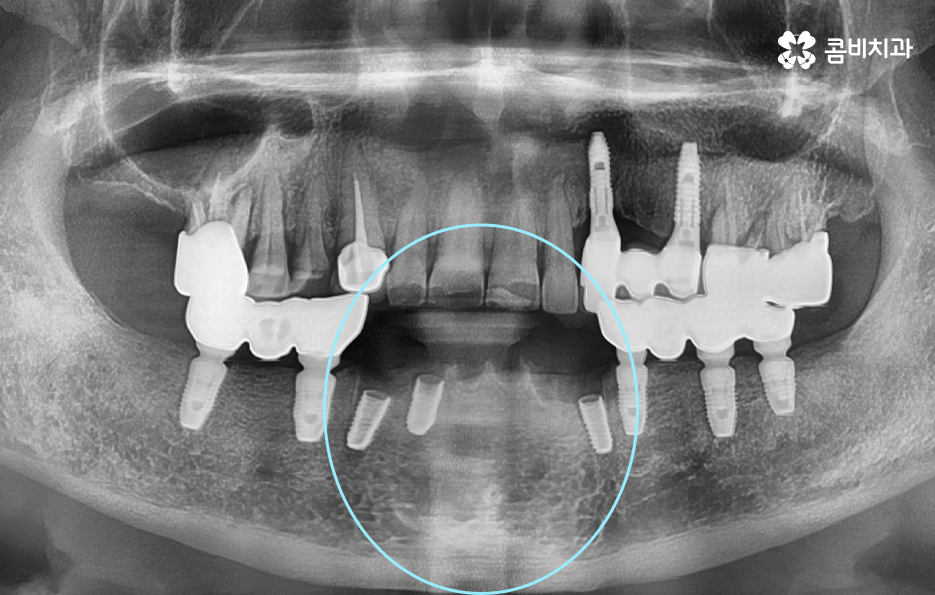

위 사진에서 보시는 것처럼 이미 치주염으로 인해 뿌리가 흔들리는 치아는 한꺼번에 여러 치아를 잃게 되었으며 기존의 임플란트 역시도 약해진 잇몸 뼈와 치료 비용 등을 감안하여 브릿지의 형태로 임플란트가 식립되어 있는 것을 확인할 수 있어요

발치후 임플란트 기간에 있어서 뼈이식이 추가 되는 경우에는 뼈이식 기간만 약3~ 6개월을 예상하는 것이 보편적이며 뼈이식을 받은 환자 분들의 경우 골유착 기간 또한 일반적인 임플란트 기간 보다는 좀더 여유있게 회복기간을 지켜보고 있어요. 다만 상태에 따라서 발치 후 뼈이식을 바로 진행하는 경우도 있고, 발치 후 뼈이식과 동시에 픽스처를 식립하여 수술을 진행하는 경우도 있어 정확한 수술 계획은 환자분의 상태에 따라 수술 계획이 달라질 수 있어요.

기본적으로 자연치아나 잇몸 자체의 문제도 복합적인 문제의 양상을 띄는 경우가 대부분이며 임플란트 치료 계획을 세우더라도 잇몸 뼈의 부족으로 인해 뼈이식을 받아야 하는 경우가 많고 임플란트 식립 개수 역시도 여러개를 식립하는 경우가 많다보니 발치후 임플란트 기간에 있어서 넉넉잡아 1년 정도를 치료 기간으로 보고 치료하는 경우도 많이 있어요